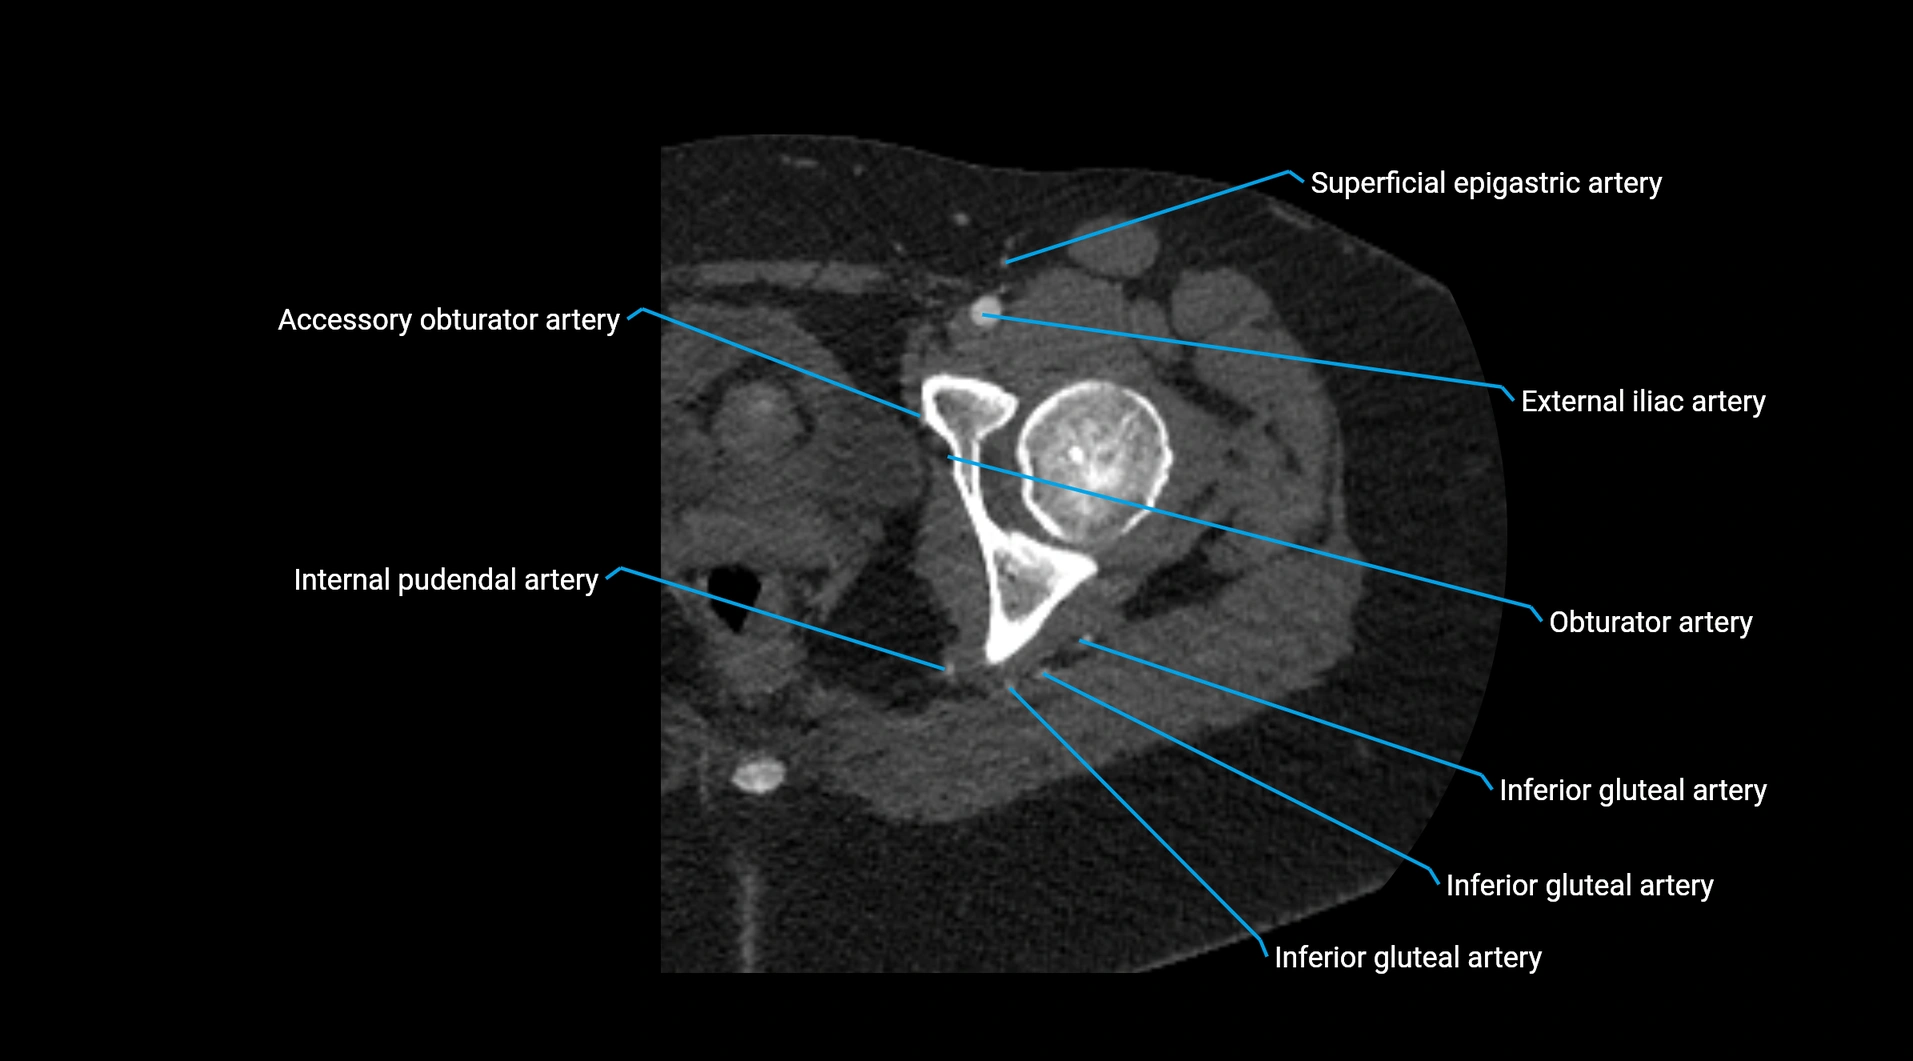

Contrast-enhanced CT (CTA):

• Gold standard for abdominal aortic imaging

• Provides excellent detail of lumen, wall, aneurysm, thrombus, and branch vessels

• Multiplanar and 3D reconstructions help in aneurysm measurement, stent graft planning, and dissection evaluation

• Detects acute rupture, traumatic injury, or occlusion with high sensitivity